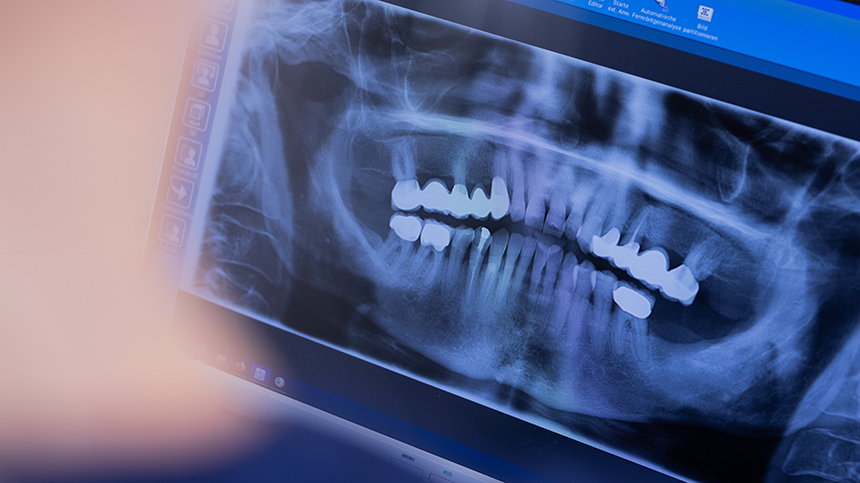

«Панорама верхней челюсти, это компьютерная томография. К сожалению, эти импланты, 30%, находятся вне кости. Не знаю, почему так получилось. Такая картина. Их придется удалять», — разъясняет челюстно-лицевой хирург, кандидат медицинских наук, руководитель клиники Севак Барсегян.

И действовать нужно быстро, ведь каждый день без зубов меняет челюстно-лицевой сустав необратимо.

«Нижняя челюсть идет вперед, носогубные складки образуются. И молодой парень, и мы видим, как будто он постарел», — говорит доктор.